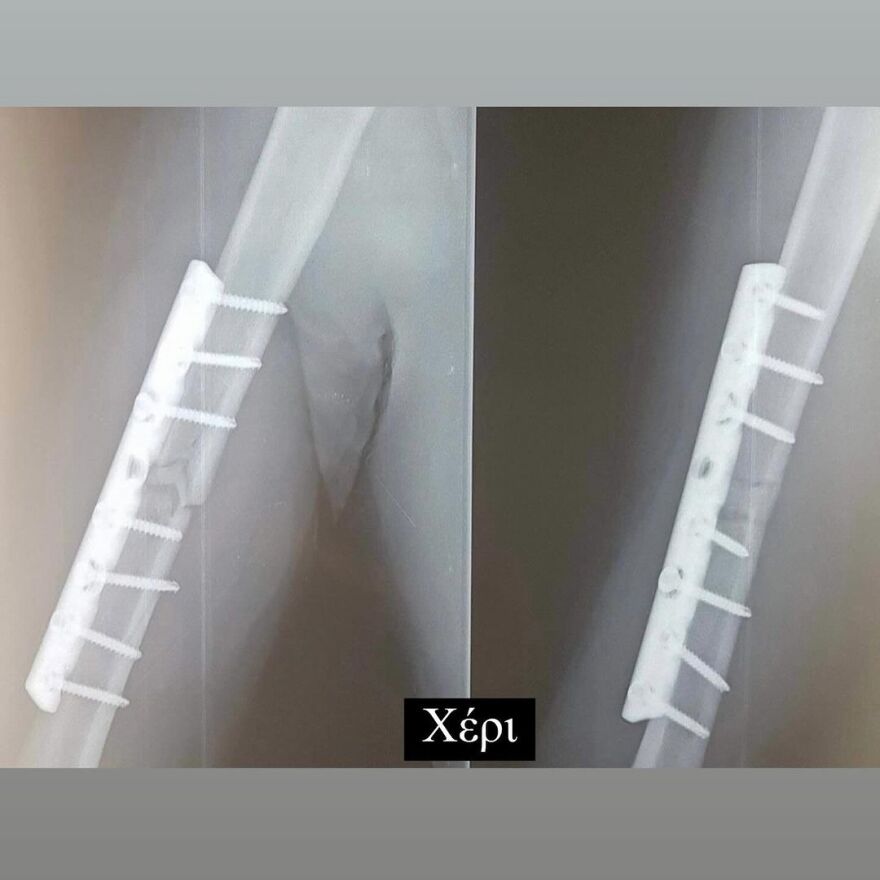

Έδειξε για πρώτη φορά τις ακτινογραφίες με τις λάμες, που έχουν τοποθετηθεί στο σώμα του μετά το ατύχημα

Σε ανάρτηση που έκανε στον προσωπικό του λογαριασμό στο Instagram, ο Ηλίας Βρεττός έδειξε στους διαδικτυακούς του φίλους τις λάμες που έχει στο σώμα του.

Συγκεκριμένα, δημοσίευσε μια σειρά από φωτογραφίες με τις ακτινογραφίες που έκανε. Σε αυτές φαίνονται οι λάμες στο χέρι, το πόδι και τη λεκάνη του.

Στη λεζάντα της ανάρτησής του έγραψε: «19/02 Αγία Φιλοθέη μου Μεγάλη η Χάρη σου!!! Σ´ευχαριστώ… 6 χρόνια πέρασαν και όλα ακόμα μοιάζουν σαν χθες… Τα σίδερα μέσα μου που για πρώτη φορα σας δείχνω στα X-rays έτσι κι αλλιώς δεν με αφήνουν να ξεχαστώ. Όμως είμαι καλά και κυρίως είμαι εδώ! Ο λόγος που το κάνω αυτό είναι γιατί κάθε χρόνο τέτοια μέρα με πιάνουν τα φιλοσοφικά μου και προσπαθώ να ξορκίσω το κακό».